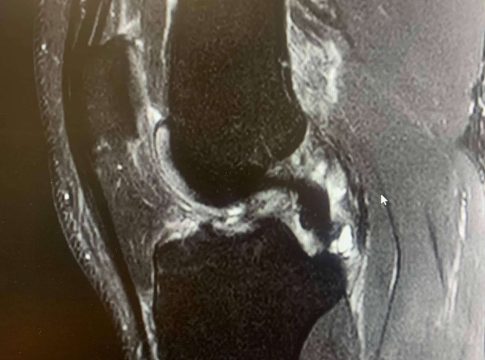

El ligamento cruzado anterior es una banda de tejido fuerte y resistente que se encuentra en la rodilla y juega un papel crucial tanto en la estabilidad como en la capacidad de control de esta articulación.

Las lesiones de LCA suelen ocurrir en situaciones en las que la rodilla está sometida a un estrés repentino y excesivo, sobre todo cuando la pierna está en apoyo y se somete a una torcedura en valgo (“metiendo la rodilla hacia dentro”) o con una torsión de la pierna hacia afuera con torsión interna del muslo, con la rodilla en flexión.

Una caída o un giro inesperado en la vida cotidiana puede causar una lesión en el LCA. Los síntomas de una lesión del ligamento cruzado anterior (LCA) pueden variar en intensidad según la gravedad de la lesión.

Derrame articular: Si el traumatólogo lo tiene que extraer mediante punción para aliviar la presión y el líquido es rojo (“hemático”), es probable que se trate de una lesión del LCA, aunque puede tener otras causas.